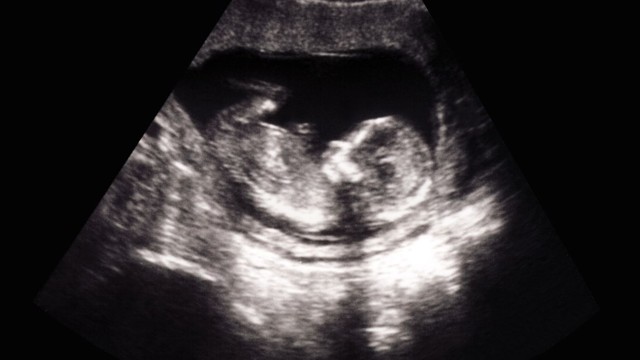

Hình ảnh siêu âm bé gái 16 tuần tuổi giúp ba mẹ theo dõi sự phát triển của thai nhi, đồng thời phát hiện sớm bất thường. Cùng tìm hiểu chi tiết trong bài viết sau!